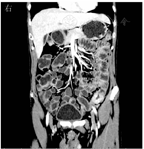

2021年4月19日完善小肠CT造影(computed tomography enterography,CTE)检查示降结肠与乙状结肠交界处可见节段性腔壁增厚、对称,管腔狭窄改变,并可见明显强化征象,未见明确分层和梳状征;所示空肠、回肠大部充盈扩张,未见明显腔壁增厚和管腔狭窄改变,未见明确异常强化征象;腹腔未见积气、积液(图2)。当日完善结肠镜+超声内镜检查,白光内镜下见直肠黏膜光滑,乙状结肠距肛门约20 cm以下可见多发不规则溃疡,伴自发性少量渗血,肠腔狭窄(图3A),无法通过,病灶处予多块深挖活检;超声内镜检查示乙状结肠局部肠壁增厚,最厚处约1.3 cm,肠壁层次结构模糊不清、呈较均匀低回声,浆膜层不完整,病变周围腹腔可见多发低回声区(图3B)。肠镜活检病理示乙状结肠黏膜表面糜烂,伴凝固性坏死,肠黏膜固有层内大量淋巴细胞增生,增生的淋巴细胞呈小到中等大小,可见异型细胞;免疫组织化学检查示增生的淋巴细胞以自然杀伤/T细胞为主,可见少量大B淋巴细胞,EB病毒编码区(Epstein-Barr encoding region,EBER)阳性,未见巨细胞病毒包涵体。

影像科叶峰副主任医师:本例患者的临床、内镜下表现和活检病理结果均缺乏特异性。当临床上对结肠溃疡的性质鉴别存在困难时,影像学往往可以提供一些线索。CTE所示肠壁增厚和强化的方式有助于鉴别诊断[6,7]。不均匀强化和不对称性的局限性肠壁增厚多见于腺癌、间质瘤或转移瘤,与患者表现不符;结合内镜下表现和活检病理结果,考虑上述疾病可能性小。分层强化(靶征)多见于炎症或感染性疾病。患者CTE未见肠壁分层强化,周围无梳状征象(提示直小血管扩张),不符合克罗恩病活动期典型表现。肠结核可表现为肠管环形增厚,肠壁黏膜不光滑(提示溃疡),呈分层或均匀一致强化,周围可见淋巴结肿大伴环形强化(提示干酪样坏死)或钙化,可见回盲瓣挛缩呈鱼嘴样。本例患者表现与此不符,且其结核感染T细胞斑点试验阴性,该病可能性小。淋巴瘤可见肠壁呈节段性或弥漫性增厚,对称,密度均匀,增强扫描可呈中度或明显强化,病灶内坏死、囊变、出血和钙化少见,肠管周围可见肿大淋巴结,沿血管走行分布。基于以上分析,结合患者CTE表现,不能排除淋巴瘤,建议再次活检。